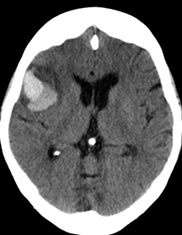

The patient undergoes a repeat non-contrasted CT brain scan (Figure 5).

Figure 5. Results of the repeat non-contrasted CT brain scan image.

Based on the non-contrasted CT brain scan image and after patient was treated with IV nicardipine to lower her current BP of 140/72 mm Hg, what is the best next step in management?

Based on the repeat CT brain scan showing acute right frontotemporal intracerebral hemorrhage and concern for post-IV thrombolytic symptomatic hemorrhage, the best next step would be to administer IV thrombolytic reversal agents. This is often done after obtaining a complete blood count, prothrombin time, aPTT, fibrinogen level, and type and cross-match followed by administration of combined cryoprecipitate and tranexamic acid or aminocaproic acid.

If IV alteplase is being infused, infusion should be stopped as soon as possible. You should refer to your institution’s IV t-PA reversal protocols to become familiar with this process and what is available. It is also important to familiarize yourself with your institutional reversal protocols for other antithrombotic agents for an acute, symptomatic intracranial hemorrhage. Of note, unless a patient is being taken for emergent neurosurgical hematoma evacuation, antiplatelet reversal with platelet transfusions has been shown to be harmful and should be avoided.9